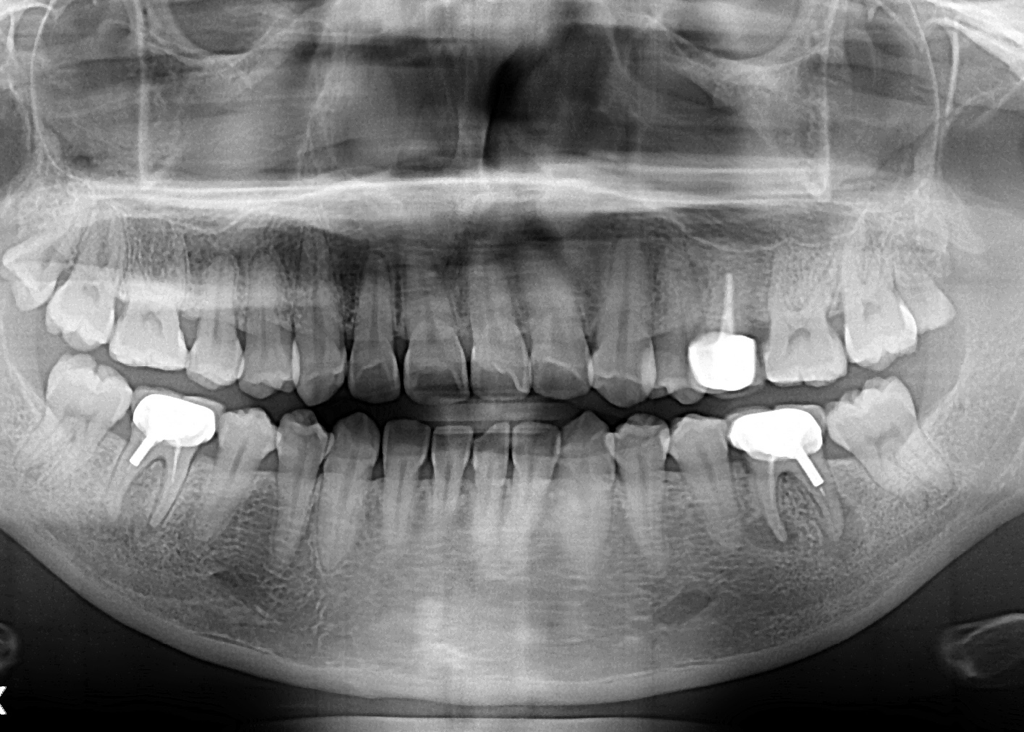

현재 왼쪽의 경우 (사진상 오른쪽) 사진상에서 확실히 염증주머니(물혹)가 잡혀 뼈를 녹이고 있는 모습이 관찰됩니다

신경치료 재치료 또는 발치가 필요한데 이전 신경치료 과정에서 기둥(포스트)를 크라운과 연결해두었기 때문에 재신경치료를 위해 크라운을 뜯는 과정에서 치아에 불가피한 손상이 가해질 가능성도 배제할 수 없습니다

치아가 깨져나가거나 하는 경우 치료 진행이 더이상 어려울 수도 있음을 감안하셔야 합니다.

오른쪽 어금니도 왼쪽보다는 아니지만 상태가 좋은 편은 아닙니다.

임플란트는 곧 치아의 발치를 의미합니다. 발치 전까지 거칠 수 있는 치료가 완전히 없는 것은 아닌데 치아의 뿌리 끝을 잘라내는 치근단 절제술이 있습니다

일단, 왼쪽은 염증이 이미 확산되어 뼈를 녹이고 있는 상태이기 때문에 치료를 지체할 수는 없습니다